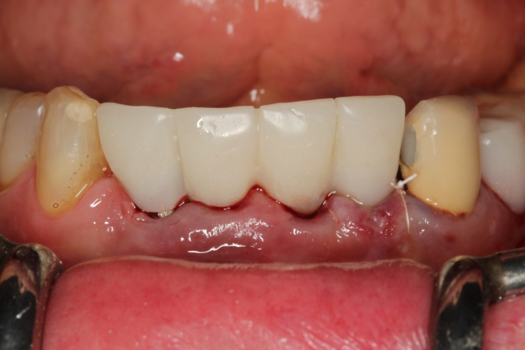

The next case follows the digital protocol for fully guided surgery and prosthetics. A CBCT radiograph, digital impression, and digital photography were the cornerstones to the success of this case. The 3D data set was electronically delivered to the dental laboratory. The data were merged and the process to develop the plan was initiated. The use of CBCT was essential in this case, particularly due to minimal space for placement of individual implants and single-unit crowns. The patient's chief concern was that she wanted to have single-unit crowns instead of fixed crown-and-bridge restorations because she was worried that she would someday find herself in an assisted-living facility; if that were to happen, she wondered, who would help floss under her bridge work? Her decision was to have single implants with individual crowns. CBCT technology is much more accurate in evaluating space maintenance and management.10 Periapicals in the past were rather close for calculating spacing; however, the CBCT identifies the buccal-lingual dimensions as well as the mesial-distal measurements. On review of the completed proposals for implant placement and provisionals, it was determined that there was sufficient spacing for implant placement to allow appropriate emergence profiles for the provisionals and then eventually the final single-unit cemented crowns. The proposal was accepted, and a 3D-printed surgical stent was fabricated, along with the PMMA provisionals (Figure 29 through Figure 35).

On the day of surgery, the plan was to extract teeth Nos. 21, 23, 24, 25, and 26, place 3.0 x 13-mm implants in the anterior region due to limited spacing, and place a 4.1 x 10-mm implant in the No. 21 extraction site. Before the extractions were performed, the No. 23 pontic was sectioned from the existing 2-unit cantilevered bridge utilizing ceramic and metal high speed rotary cutting burs ZR 6881 and H34L (Komet-USA), respectively. After removal of the pontic and extractions, the surgical guide was verified to be seating positively (Figure 36 through Figure 38). Surgical guide protocol was followed, and all implants were successfully placed and torqued to a value of greater than 35 Ncm (Figure 39 and Figure 40). All implants were placed without flapping, with the exception of No. 23. The flap was elevated to reposition lingual keratinized tissue facially for enhanced esthetic tissue profile. The implants were then prepared with a high-speed carbide bur (Komet-USA) with copious amounts of water (Figure 41 and Figure 42). The one-piece 3.0-mm diameter implant served the needs of the patient's spacing requirements. Inter-occlusal space requirements and path of draw were verified. The PMMA provisionals were air abraded and relined with crown-and-bridge material (Figure 43 through Figure 45).

Fig 43. PMMA provisional digitally fabricated and milled.

Figure 43

Fig 44. Splinted PMMA seated.

Figure 44

Fig 45. Occlusal view of seated PMMA provisionals.

Figure 45